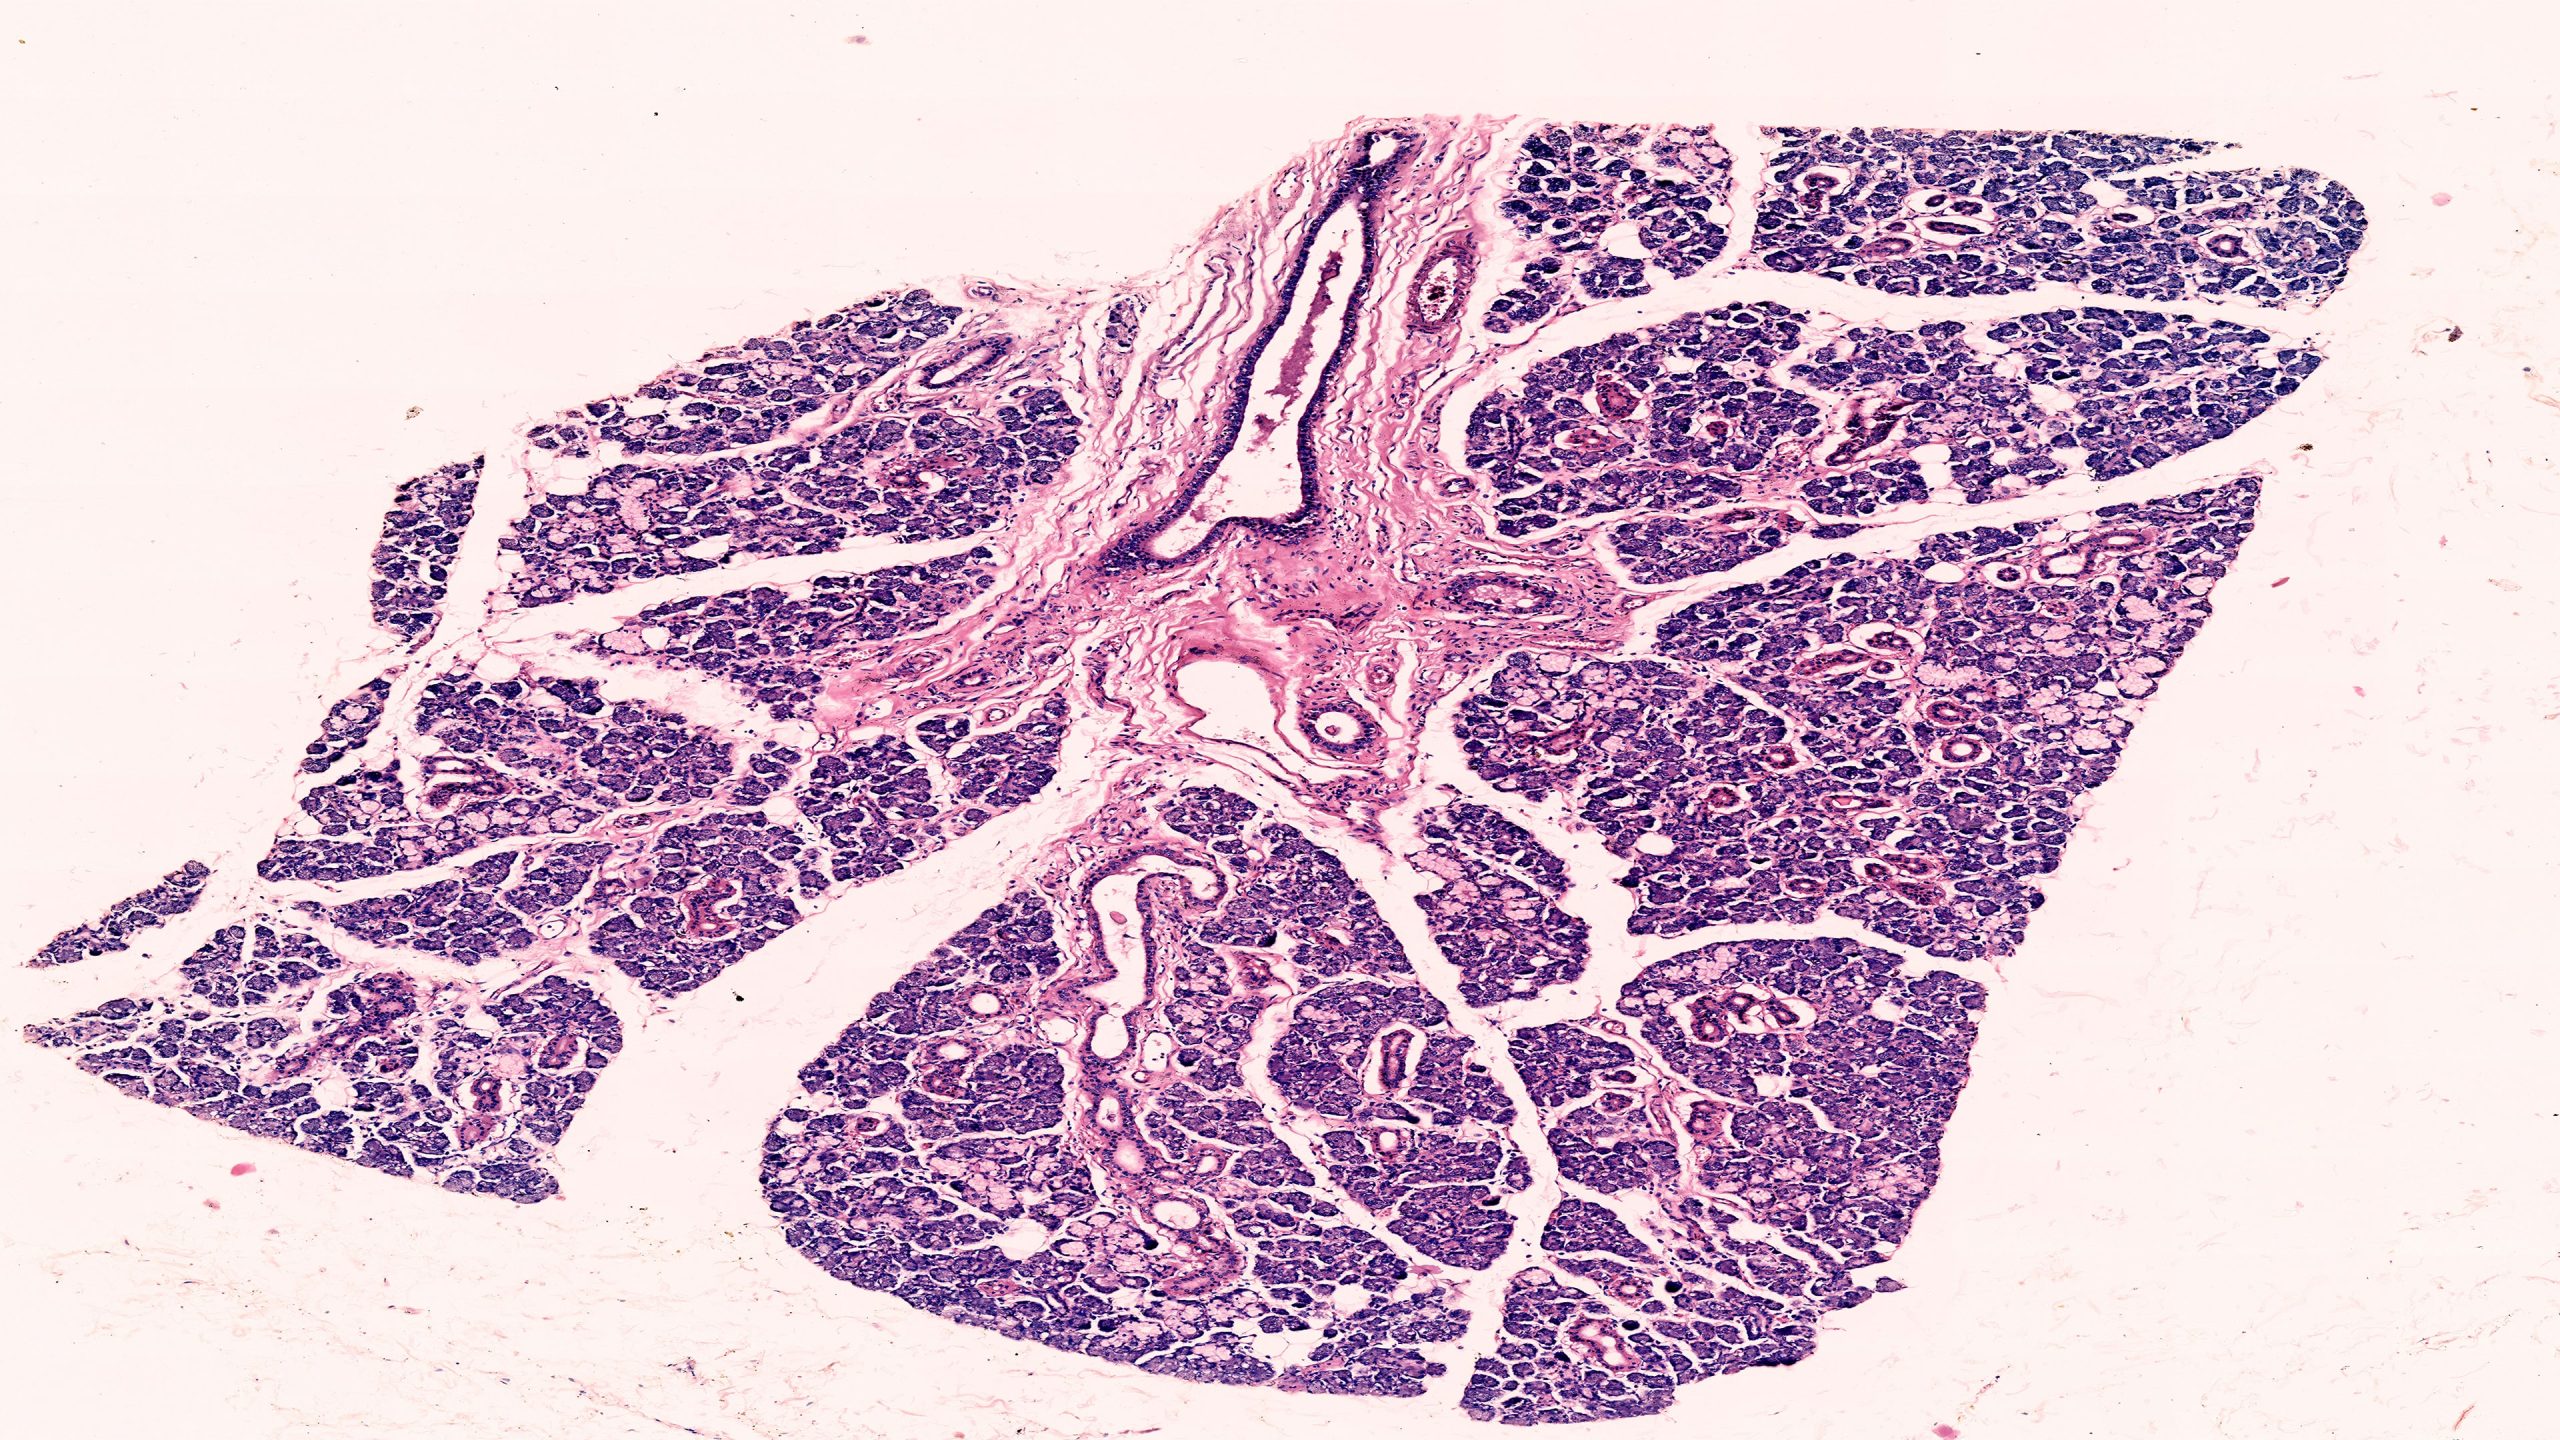

Mucous Salivary Gland 4X